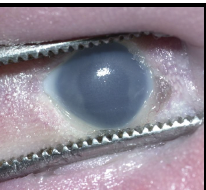

icteric sclera

blue sclera